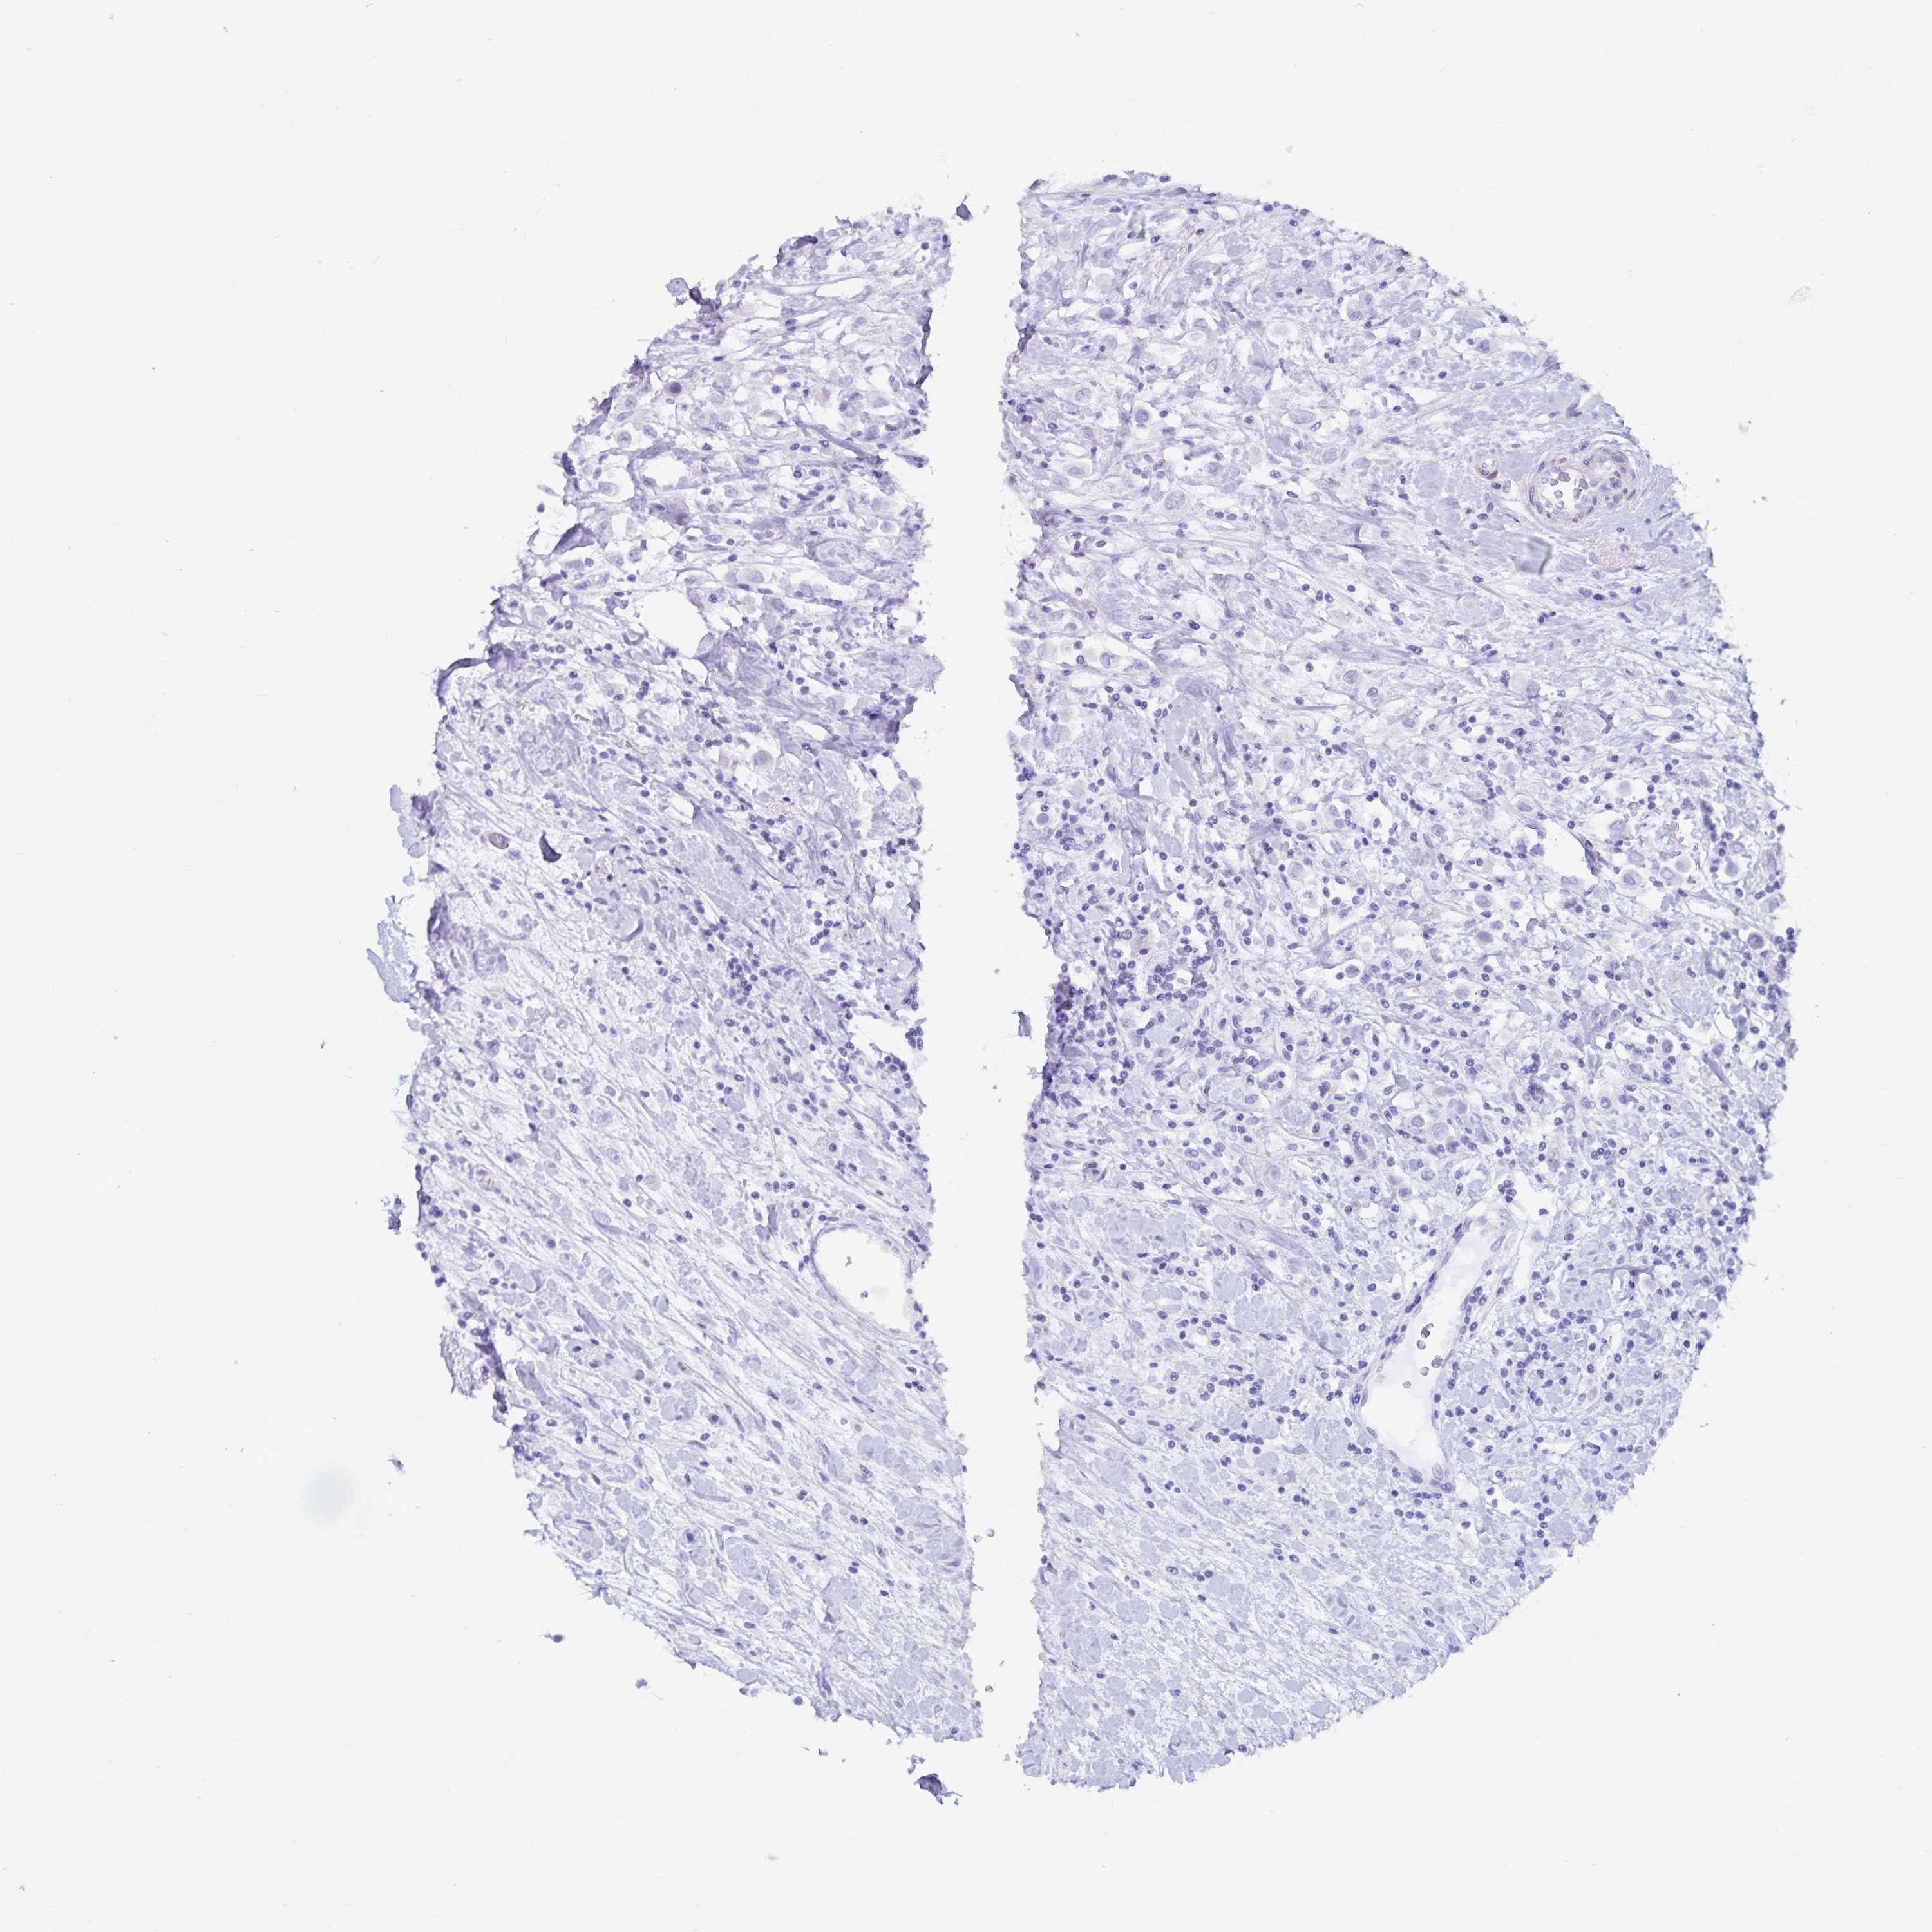

CANCER BREAST CANCER Show tissue menu

Breast cancer

Human cancer